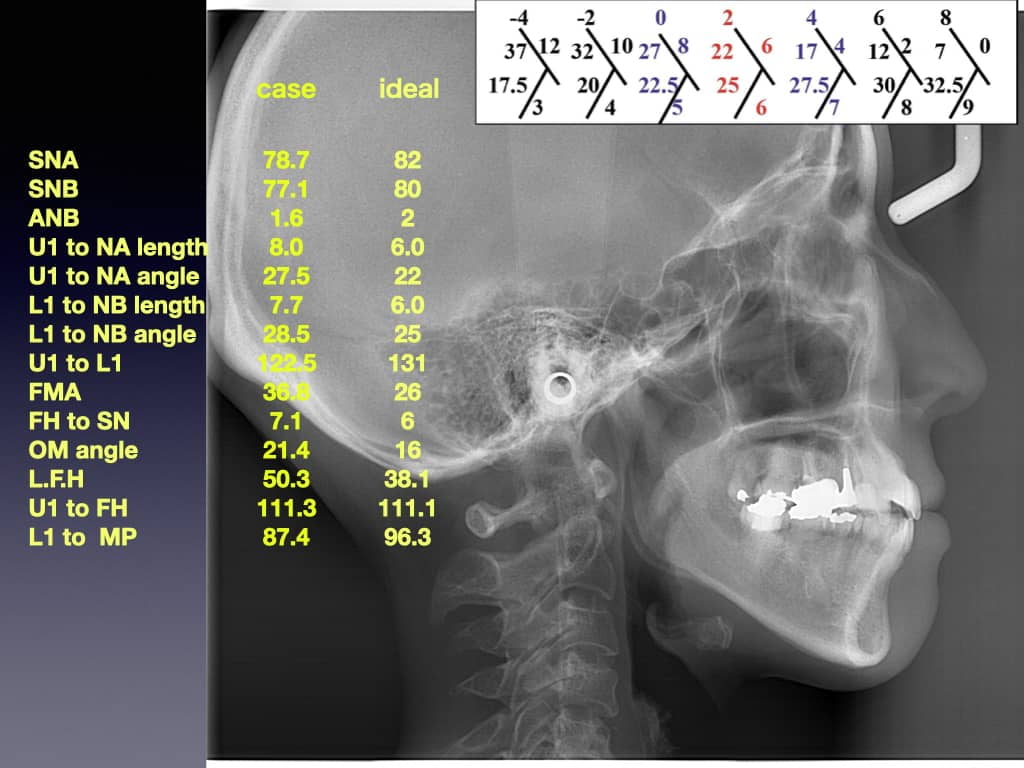

矯正治療において大切なことは、それぞれのお顔や口元に合わせて前歯(特に上の前歯)の位置を考えて逆算して設計することです。当院では矯正治療前に全ての患者さんに2時間にもわたる正確な資料採得を行います。

そして正確な資料をもとに客観的に判断する材料として数値を取り出します。最後に歯科医師の感覚的、経験的な判断も考慮しながら慎重に設計をします。